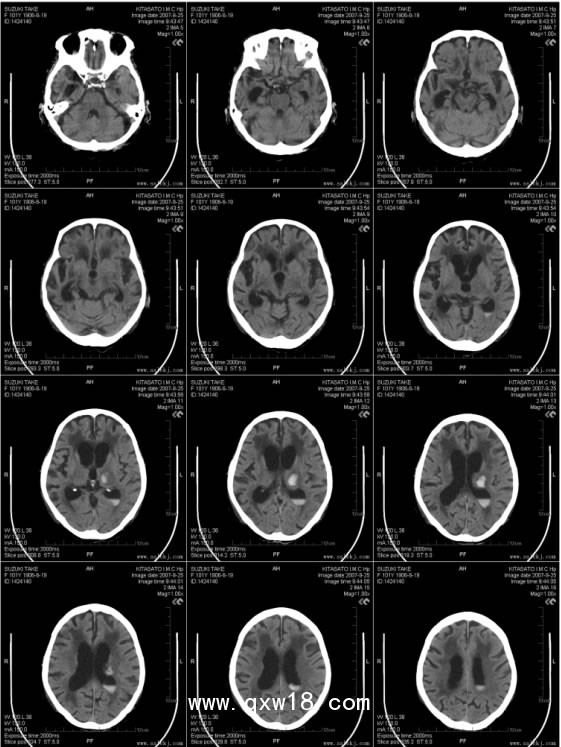

醫(yī)用藍(lán)基膠片?CT.CR.DR?放射科產(chǎn)品說(shuō)明:

【適用用途】本品適用醫(yī)療影像的數(shù)字化輸出,可用于打印X光片、CT、MRI、三維重建等圖文診斷報(bào)告,適用于愛(ài)普生、佳能等噴墨打印機(jī)。